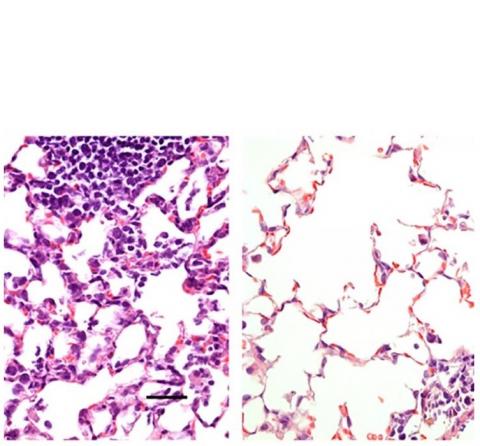

Les chercheurs de l'Université de Washington à Saint-Louis ont mis au point un vaccin anti-COVID-19 délivré par le nez et qui protège les souris du virus. L'administration nasale (tissu pulmonaire de droite sur visuel) produit une réponse immunitaire plus étendue que l'injection intramusculaire (tissu pulmonaire de gauche). Prochaine étape, tester le candidat sur des primates non humains puis chez l’Homme, pour valider sa sécurité et son efficacité.

Les chercheurs qui ont comparé les 2 modes d’administration (injection intra-musculaire et administration nasale) chez la souris, constatent que la voie d'administration nasale a empêché l'infection dans les voies respiratoires supérieures et inférieures - le nez et les poumons - suggérant que les personnes vaccinées ne propageraient pas le virus et ne développeraient pas d'infection.